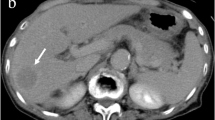

a–c Attenuation-correction artifact due to chemoembolization agent. A 69-year-old man received transcatheter arterial chemoembolization (TACE). Attenuation-corrected PET/CT images (a, b) reveal increased FDG uptake within Lipiodol deposition in segment 5 (arrows), but non-attenuation-corrected PET image (c) shows no abnormal FDG uptake and is indistinguishable from normal liver parenchyma. These findings provide an example of an overestimation artifact from Lipiodol

In this study, we observed Lipiodol-induced attenuation-correction artifacts in two patients, which were positive on attenuation-corrected images and negative on noncorrected images. Chemoembolization materials cause an overestimation of PET activity when using CT information for PET attenuation correction [30]. Thus, non-attenuation-corrected PET images should be considered to avoid a misdiagnosis in patients treated with TACE.